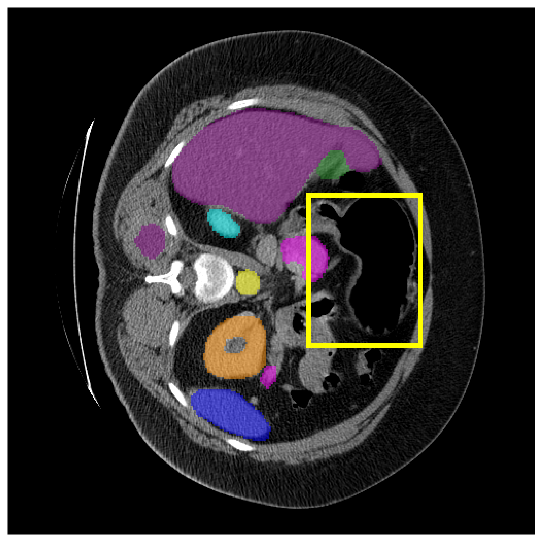

4.3.2 Visual Comparisons

Visualization of our method on the Synapse and ACDC datasets is shown in Fig. 3(a) and Fig. 3(b). For the Synapse dataset illustrated in Fig. 3(a), FCT failed to accurately segment SM and GB, while MERIT achieved precise segmentation of SM but struggled with GB. In contrast, our method achieved accurate segmentation of both SM and GB. Regarding the ACDC dataset shown in Fig. 3(b), while previous methods achieve comparable segmentation of the Myo and LV to the GT, they exhibit noticeable errors on the RV, including invasion into adjacent organs and misrecognition. On the other hand, our method accurately segments across all three structures Myo, LV, and RV, performing as precisely as the GT. We demonstrate the superiority of our method quantitatively and qualitatively.